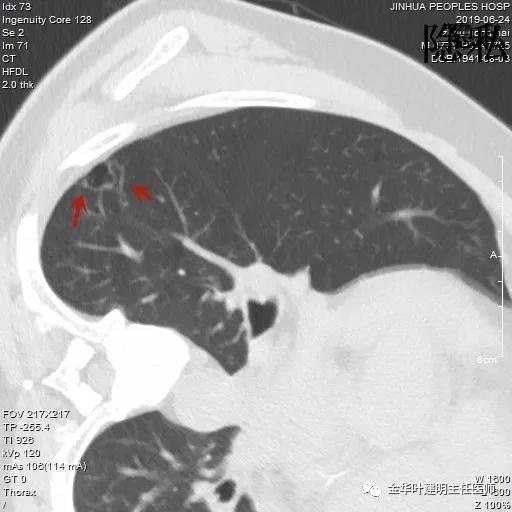

如果我们把各个时候的片子放在一起对比,就会发现右下叶背段的空腔性病灶是从无到有,并逐渐进展的:

逐渐进展的空腔性病灶,特别边缘还是磨玻璃样的,需要特别当心,虽然有的层面看上去似肺大泡,但仍需我们提高警惕,注意必要的随访复查。